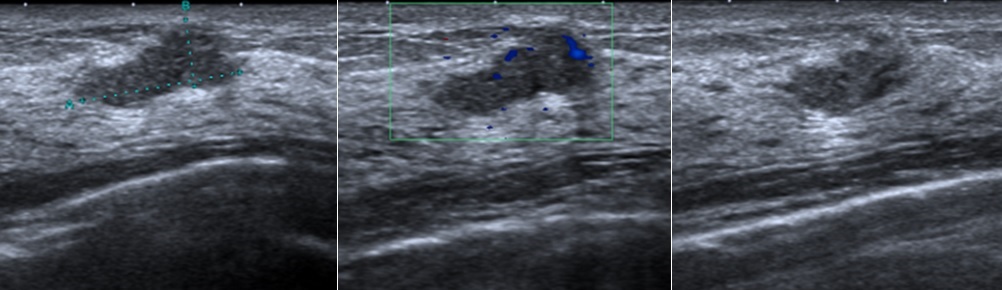

上述兩位患者透過理學檢查與超音波掃描後,確定屬於腿後肌症候群,都在腿後肌近端肌腱於坐骨粗隆接骨點的位置出現部分撕裂情形,且腿後肌肌肉中段處皆有多處激痛點,B小姐的肌肉緊繃甚至壓迫到坐骨神經,造成局部麻木。

醫師除了依據運動傷害的治療原則,先建議患者相對休息,避免進行造成傷害的運動,另外採取超音波導引注射的治療方法,注射玻尿酸於肌腱撕裂點,並以葡萄糖水針對肌肉激痛點注射,緩解肌肉緊繃的症狀。針對B小姐有局部麻木症狀,醫師施予坐骨神經神經旁注射,解除了該處神經壓迫的情形。